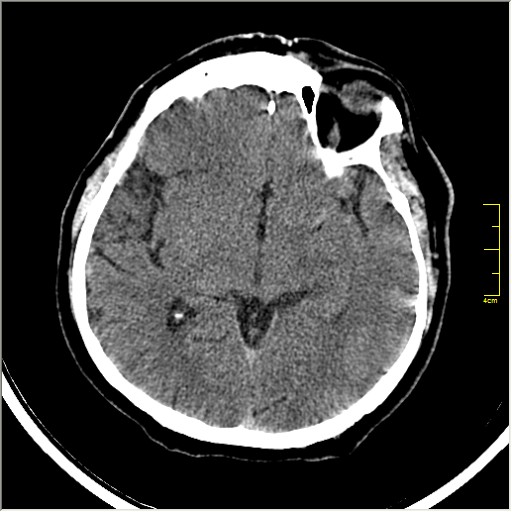

Пациентка Д. 64 года. Поступила с диагнозом ОНМК ???, жалобы на онемение и слабость в левой половине тела.

Ответ: Обратите внимание на правую среднемозговую артерию (MCA); М1 сегмент гиперденсен; сравните с другой стороной.

Этот признак называется [Dense MCA sign]; за счёт наличия тромбоза в её просвете. Этот признак является одним из ранних указующих КТ признаков при ишемическом инфаркте головного мозга. Более подробно об этом вы можете прочитать здесь: http://www.radiologyassistant.nl/en/483910a4b6f14.